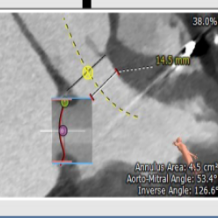

二尖瓣位评估

术前经详尽评估患者病情,通过CT重建测量瓣环直径、左室流出道面积。综合评估决定对该病例采用经静脉途径行二尖瓣“瓣中瓣”手术。既往植入25#St jude生物二尖瓣,测量支架内径22.9mm,选用23#SAPIEN 3球扩式瓣中瓣。虽手术过程异常艰难,但最终瓣中瓣植入位置理想,左室造影及经食道超声观察无明显瓣中及瓣周反流。瓣中瓣植入后观察左房峰值压明显下降,二尖瓣平均跨瓣压差降至3mmHg。